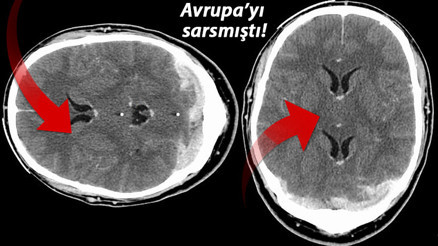

#ABDKüresel çapta başlayan koronavirüs aşı kampanyalarına devam edilirken ortaya çıkan ciddi yan etki vakalarından sonra birçok Avrupa ülkesi tarafından kullanımı askıya alınan AstraZeneca aşısıyla ilgili flaş bir gelişme yaşandı. Avrupa İlaç Ajansı'nın (EMA) açıklamalarından sonra aşının uygulamasını askıya alan tüm ülkeler teker teker kararlarından vazgeçtiklerini açıkladı. Aşı üreticisinden ve bilim insanlarından ise tartışma yaratan yan etki karmaşasıyla ilgili flaş açıklamalar peş peş geldi.